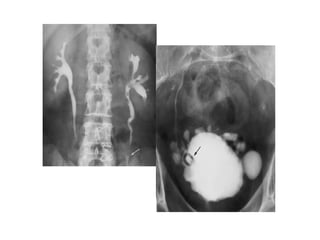

X-QUANG HỆ NIỆU

KUB

• Mục đích:

Đánh giá vôi hóa bất thường của hệ

niệu

Đánh giá tình trạng ổ bụng

Bất thường hệ thống xương

—Kỹ thuật:

Chuẩn bị bệnh nhân:

Tư thế BN : nằm ngửa, phim chụp AP

Yêu cầu: lấy từ cực trên thận đến hết

khớp mu.

• Phân tích kết quả:

- Thận

- Bất thường đậm độ

đường niệu

- Dải mỡ cơ thắt lưng

chậu

- Tình trạng ổ bụng

- Hệ thống xương

• Hạn chế:

- Độ nhạy và độ đặc hiệu phát

hiện sỏi hệ niệu không cao ( ≤

60%) do : sỏi nhỏ, sỏi không cản

quang, trùng lắp vào xương…

- Cần phân biệt với nhiều

nguyên nhân vôi hóa khác trong

ổ bụng ( Vôi hóa TM chậu:

Phlebolith,…)

UIV

Khảo sát

hình thái và

chức năng hệ

niệu.

• Kỹ thuật chụp:

- Chuẩn bị bệnh nhân: thụt tháo

- Chụp phim KUB ngay trước khi chụp UIV.

- Liều thuốc cản quang: 1-2ml/kg cân nặng.

- Phim sớm 01 phút :nhu mô và đường bờ

thận.

- Phim thì 05 phút : đài thận, bể thận.

-Phim thì 15 phút : bể thận, niệu quản.

-Phim thì 30 phút : bàng quang